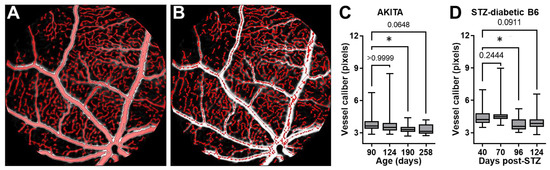

It has been established that reduced caliber (diameter) and narrowing of retinal vessels occurs in association with DR [24,25]. To further corroborate the above FA-DF findings on retinal vascular leakage and further demonstrate additional benefits of longitudinal imaging studies by this noninvasive method, we assessed changes in the caliber of retinal vessels in longitudinal images acquired in the same diabetic AKITA and B6 mice of the above studies. We performed the vascular caliber (diameter) analysis according to our previous description [19,26]. In brief, automatic detection/selection of retinal vessels was done using built-in object selection algorithms in Volocity software. The selection was based on the green fluorescence intensity in images using a threshold of 1 to 3 times the standard deviation of the peak of noise signal in the first images acquired after injecting the mixed dyes in each mouse during the repeated imaging sessions in the longitudinal studies. Local contrast adjustment to correct for spectral aberration at the edge of vessels (vascular wall) and a noise removal step with a “fine filter” were included before measuring the vessel diameter (Figure 4A). Following the objects’ selection, the “skeleton” of the vascular tree was then automatically generated by the software (Figure 4B), based on which the “skeletal diameter” (vessel caliber) measurements were returned for all identified “objects” (vessels) within the image, including the central and peripheral retina. The analysis was performed on longitudinal images acquired in the same mice without image registration since we did not intend to measure changes in individual vessels. The results, however, showed a significantly reduced median caliber of retinal vessels in association with DR progression and the above-measured increases in the retinal vascular leakage in both mouse models (Figure 4C,D).

Figure 4.

Changes in retinal vessel caliber during DR progression detected and quantified in longitudinal FA-DF studies. (A) Representative fundus image showing automatic detection and selection of retinal vessels in Volocity software based on the green fluorescence intensity in the analysis of vascular caliber (diameter). (B) Outline of the “skeleton” of the retinal vascular tree corresponding to the retinal vasculature detected/selected in A that was used to measure the “skeletal diameter” (vessel caliber) of all identified “objects” (vessels) within the image. (C and D) Longitudinal measurements of vessel caliber in (C) the diabetic AKITA mice from age 90 to 258 days (n = 3–5 mice/time-point) and (D) STZ-diabetic B6 mice at 40, 70, 96, and 124 days after STZ treatment (n = 3–8 mice/time-point). Caliber measurement units are shown in pixels since the tiff images were not calibrated for pixel size. Data are shown as Box and Whiskers with error bars representing the minima and maxima. Horizontal lines inside the boxes represent the median. Data were plotted and analyzed in GraphPad Prism. Pairwise comparisons were performed by one-way ANOVA followed by Dunnett’s multiple comparison test at each time point compared to the earliest time point in each series. Asterisk (*) denotes significance with p < 0.05, and numerical p values are shown when significance was not reached. Loss of significance at the latest time points in both models was likely due to reduced numbers of mice in association with age and increased attrition due to advanced diabetic complications.